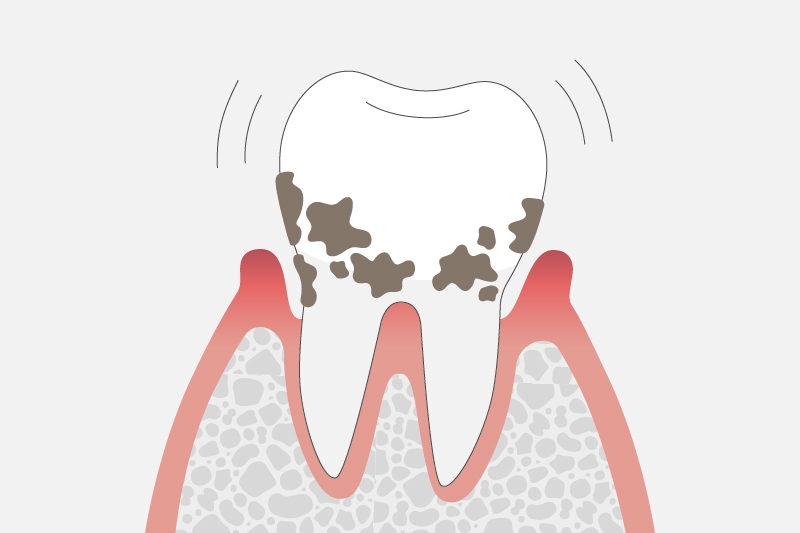

重度歯周炎

(歯周ポケットの深さ7mm以上)

歯を支えている歯槽骨が2/3以上溶けた状態です。

歯の周りを指で押すと白い膿がにじみ出て、口臭が強くなる場合もあります。歯磨きの際には頻繁に出血するようになり、歯が動揺して硬いものが噛みにくくなることがあります。放置してしまうと、歯が自然と抜け落ちるケースもあります。